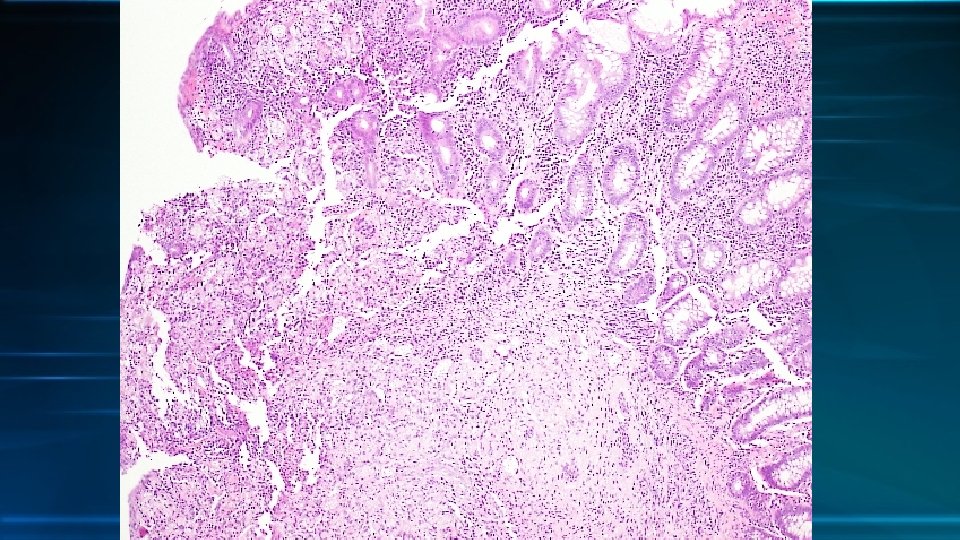

• 3 pieces of colonic tissues with ulcers • The ulcer is infiltrated by lymphocytes, plasma cells, epitheloid histiocytes, some eosinophils and neutrophils. Multinucleated giant cells are also present. • There abundant small round yeast liked organism in the infiltrating histiocytes. Viral cytopathic cells, comprising intranuclear and intracytoplasmic inclusions are occasionally seen.

Pathological diagnosis • Granulomatous inflammation with ulcer • Presence of CMV viral inclusion • Presence of fungus, morphologically compatible with cryptococcosis